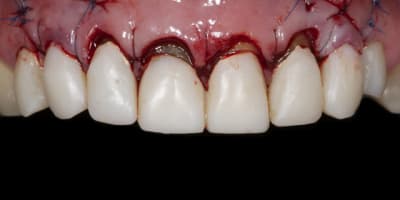

Alors j'ai commencé le traitement:

-ext 24 car mobilité type 2 + implant immédiat + couronne prov. en sous occ.

-Démontage difficile des ccm, mais surprise, traitement endo relativement mou et donc a priori pas trop délicat a reprendre.

-couronnes prov.

Évidemment tu as parfaitement raison c'est pourquoi lors de la confection des prov sur 13-23 je n'ai pas touché la racine pour adapter les prov. Ainsi lors de la chir , j'ai effectué une plastie vestibulaire radiculaire qui a permis de déplacer coronairement la limite prothetique de 2 mm env..

Ainsi j'ai pu effectué classiquement un conj enf.conjointement a un allongement de couronne de 12 à 22.